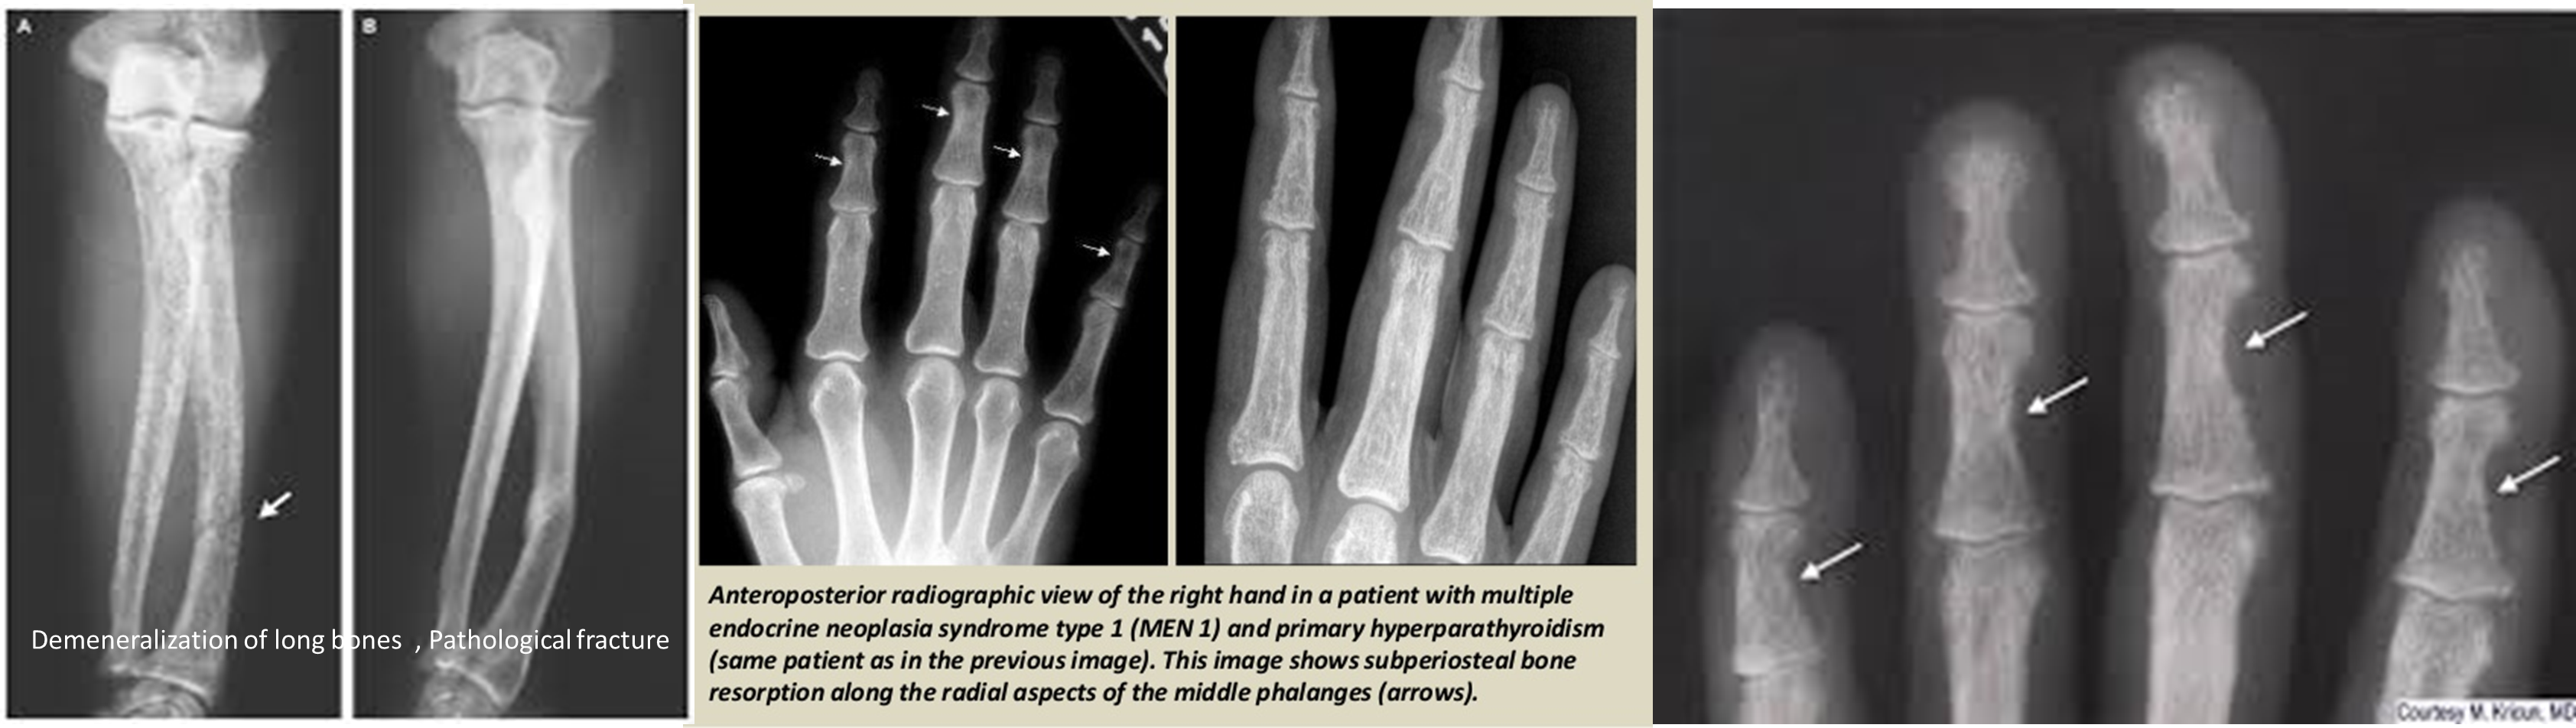

- Sub-periosteal bone resorption (most specific finding)

- Sub-periosteal resorption: middle phalanges, tibial shaft

- In hand, sub-periosteal bone resorption .This change usually happen in the middle phalanges, radial aspect in the 2nd or 3rd finger.

Sub-periosteal bone resorption

- Most useful sign

- Virtually Diagnostic

Subperiosteal bone resorption (straight arrow), resorption of the tip of the terminal phalanx and the altered bone architecture. Arterial calcification is also present (curved arrow).